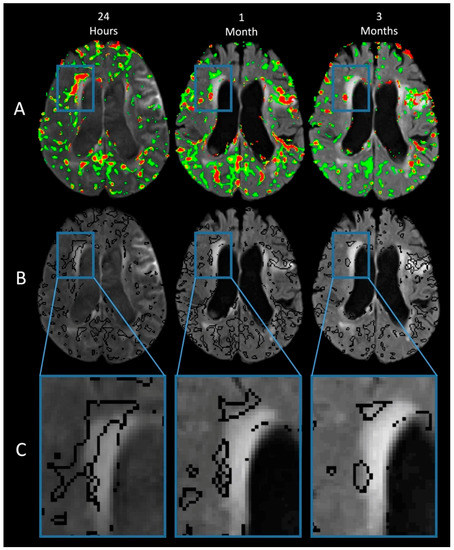

3.1.1. Imaging Findings